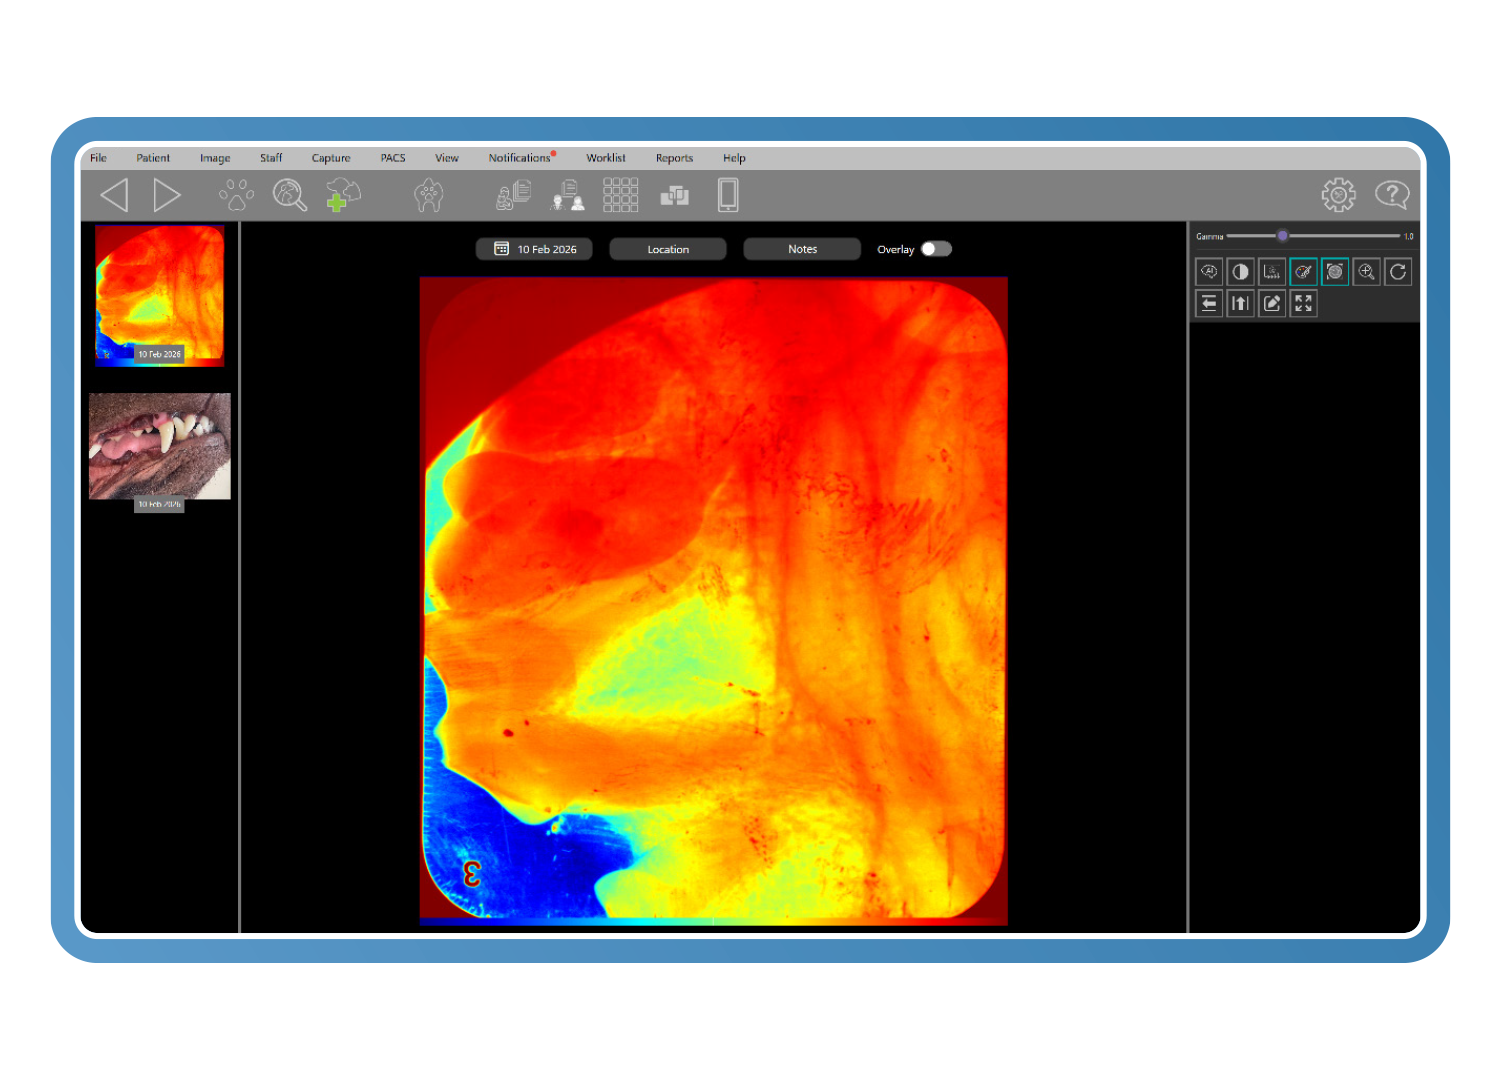

Herramientas diagnósticas específicas para veterinaria

Las herramientas avanzadas de imagen veterinaria mejoran el detalle diagnóstico incluso a partir de imágenes subóptimas. El análisis de Clarity detecta cambios con una diferencia de contraste de tan solo un 2 %, mientras que los filtros inteligentes y la visualización en pseudocolor revelan la pérdida ósea y los detalles periodontales, reduciendo las repeticiones y convirtiendo imágenes de baja calidad en imágenes diagnósticas.